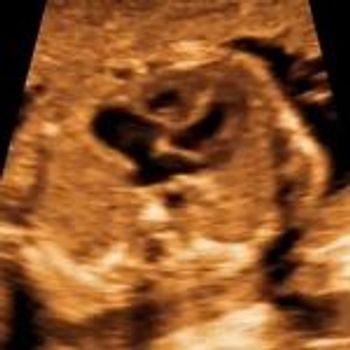

QUIZ: These images are of the fetal heart reveal an abnormality. Can you identify it?